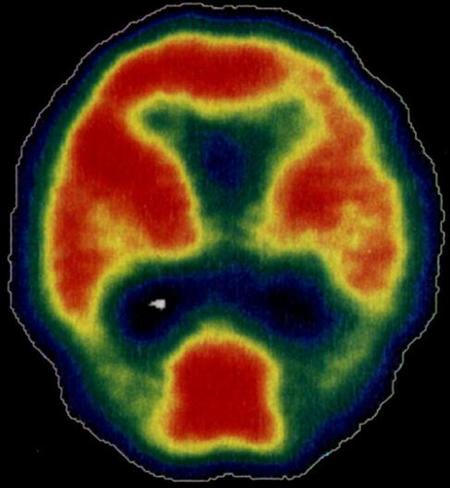

• Second, ACTRA aims to use innovative and advanced imaging techniques to better understand the link between cardiovascular risk, neurophysiology, and imaging markers of brain structure and function, and dementia related neuropathology cognitive decline as part of vascular and Alzheimer's dementia. For example, some of the projects will focus on cardiovascular and cerebrovascular link through neuroimaging methods such as MRI, SPECT (see figure below) and PET as well as researching the best methods of image analysis and of modelling imaging and other data.